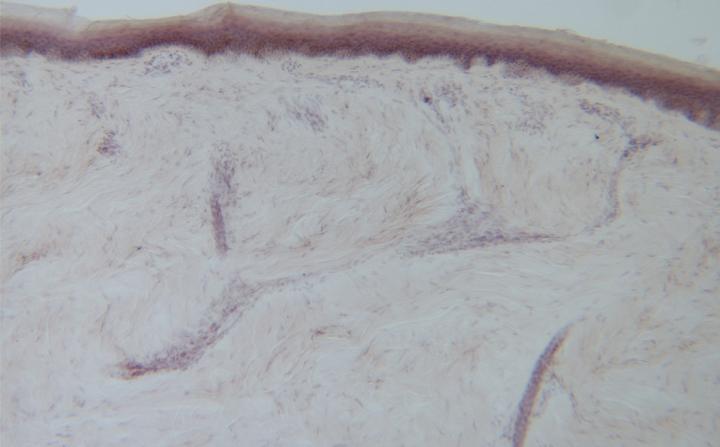

Each subject had skin biopsies taken from their outer ankle and upper thigh. The biopsies were thinly sliced and stained with a dye called Congo red that allowed the researchers to view the protein clumps in the layers of skin or within the sweat glands and pilomotor muscles (those that cause goose bumps) under the microscope. These red protein clumps looked yellowish-green when observed with a polarized lens distinguishing them from other structures in the skin sample.

Researchers observed the protein clumps in 14 people with symptoms of neuropathy and the disease and in two people with the disease but without accompanying neuropathy symptoms. The protein clumps weren't seen in any of the healthy controls or in samples from people with diabetic neuropathy.

Based on their results, Gigi Ebenezer, M.B.B.S., M.D. , assistant professor of neurology and the first author on the study, reported that protein clumps were detected in 70 percent of cases and 20 percent of patients who carried disease-causing genes but hadn't yet developed symptoms. None of the control cases showed amyloid.

The average disability score in healthy participants was 0.2. In patients with transthyretin amyloidosis but no symptoms, the average score was 4.4 and in patients with the disease and neuropathy symptoms the average score was 31.8. Healthy controls had an average of 0 percent protein clumps in their skin samples, while those with transthyretin amyloidosis but no symptoms had an average of 0.4 percent protein clumps and symptomatic patients with the disease had an average of 26.3 percent protein clumps. Higher percentages of protein clumping corresponded to greater disability in people with transthyretin amyloidosis.